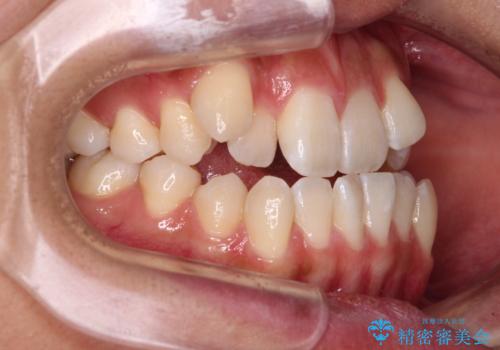

- 前歯の開咬と、上顎前歯の八重歯やデコボコを気にして来院された患者様です。

上顎歯列が狭窄していたため、急速拡大装置により上顎骨を側方に拡大し、その後ワイヤー装置にて矯正治療を行うこととしました。